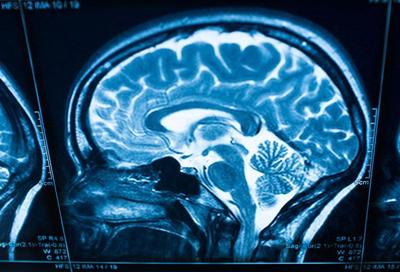

据侨报纽约网报道,纽约医生警告称,新冠病毒可能会导致30岁至40岁没有严重疾病的成年人突然中风(stroke)。据纽约邮报报道,美国有线电视新闻网报道称,西奈山医疗系统(Mount Sinai Health System)医生们认为,越来越多的证据表明,新冠病毒可以使血液以非正常方式凝固,导致通常中风低风险人群中风的几率上升。

神经外科医生奥克斯利(Thomas Oxley)称,“新冠病毒似乎会造成大动脉凝血,导致中风重症。”

奥克斯利及其同事称,有记录他们通常治疗的50岁以下中风患者每月少于两例,但在新冠疫情爆发的这两周内,他们已收治了五人。这些研究发现将发表在《新英格兰医学杂志》上(New England Journal of Medicine)。

奥克斯利称,“我们的报告显示,在过去两周年轻患者突发中风的发病率增加了7倍。大多数患者都没有既往病史,但家中有轻微或无症状新冠感染者。”